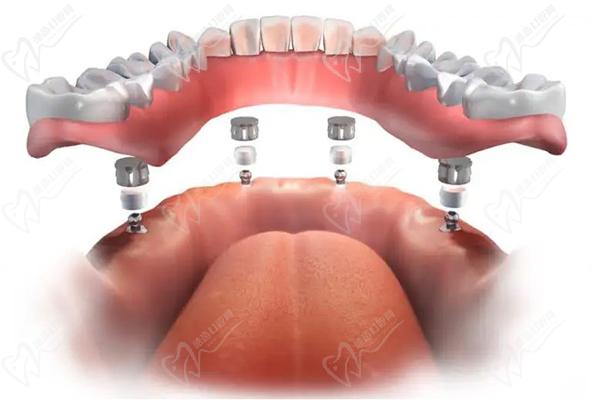

綜上,上下牙掉了10顆是做種植牙更好的。需要到正規(guī)口腔醫(yī)院進(jìn)行詳細(xì)的檢查,確認(rèn)剩下的牙齒是否堅(jiān)固穩(wěn)定,是否需要拔除,醫(yī)生會(huì)根據(jù)患者的實(shí)際情況制定更加合理的種牙方案。采用先進(jìn)的all-on-4、all-on-6即刻負(fù)重微創(chuàng)種植技術(shù),僅需要4-6顆植體就能修復(fù)好半口牙,更能當(dāng)天種牙當(dāng)天戴牙冠,相當(dāng)舒適便捷!

穿顴種植恢復(fù)半口牙